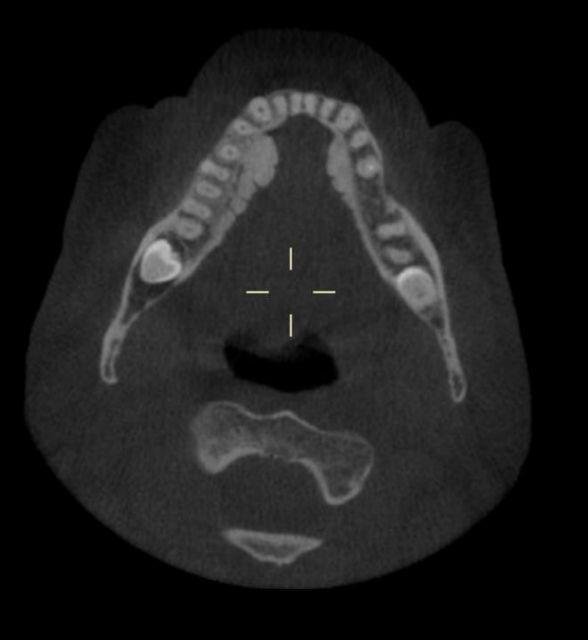

What type of slice is seen on this CBCT?

A

Axial